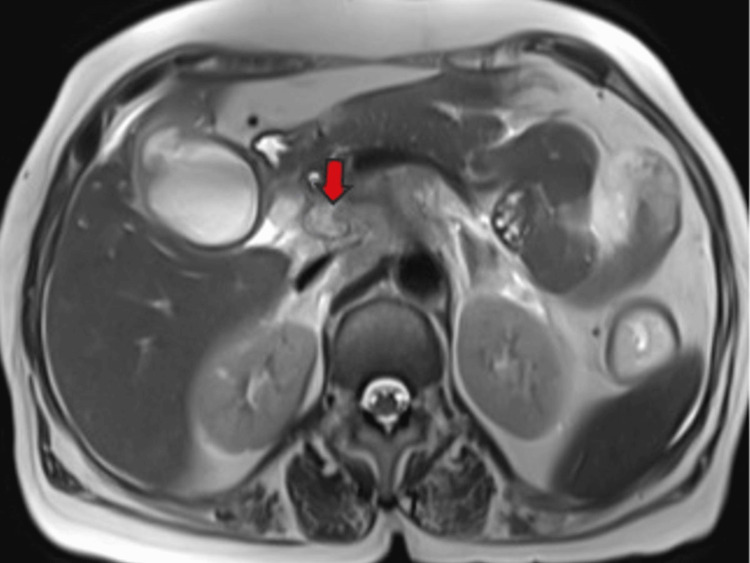

Magnetic resonance (MR) abdomen imaging with MR cholangiopancreatography (MRCP) revealed an overdistended gallbladder with circumferential wall thickening measuring 4 mm. Bile appeared hypointense on T2-weighted imaging (T2WI), indicative of sludge or thick material, with diffusion restriction on diffusion-weighted imaging (DWI) and low apparent diffusion coefficient (ADC) values. A 7 mm defect was noted in the body region, with T2 hyperintense pericholecystic fluid collection demonstrating diffusion restriction adjacent to the body. Mild dilatation of the IHBR was observed in both the right and left lobes. The CBD measured 8 mm in diameter, with narrowing of the mid-CBD due to circumferential wall thickening measuring 4 mm. The remainder of the CBD appeared normal in caliber (Figures 9–10).

These findings were suggestive of a stricture in the mid-CBD, likely neoplastic (cholangiocarcinoma), resulting in proximal biliary obstructive dilatation. Additionally, the gallbladder exhibited changes consistent with empyema and contained perforation. Multiple metastatic lymph nodes were observed in the retroperitoneum and porta hepatis, along with multiple lung metastases.